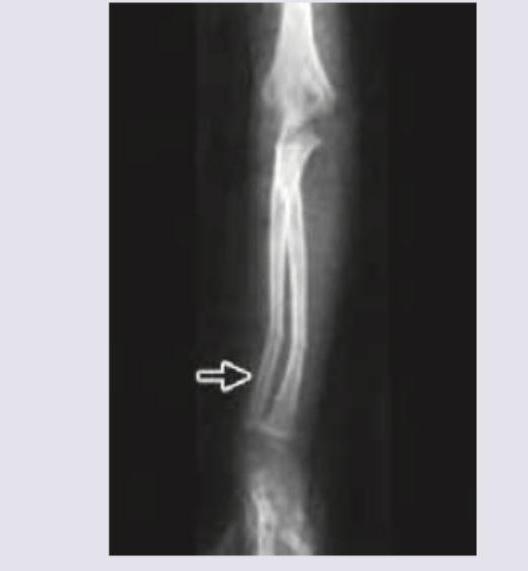

Explanation: ***Greenstick fracture*** - The X-ray image shows an **incomplete fracture** where one side of the bone is broken and the other side is bent, which is characteristic of a greenstick fracture. - This type of fracture is common in children because their bones are **more flexible** and less brittle than adult bones. *Nonunion* - **Nonunion** refers to the failure of a fractured bone to heal after a sufficient period, typically presenting with persistent pain and mobility at the fracture site long after the injury. - This image shows an **acute fracture** with no signs of attempted or failed healing. *Malunion* - **Malunion** occurs when a fractured bone heals in an anatomically incorrect or deformed position. - The image depicts an **acute fracture** immediately following injury, not a healed but malaligned fracture. *Torus fracture* - A **torus (buckle) fracture** is a subtle fracture where the bone cortex buckles but does not break through completely. - This image clearly shows a **distinct break** in one cortex and bending of the other, which is beyond a simple buckle.